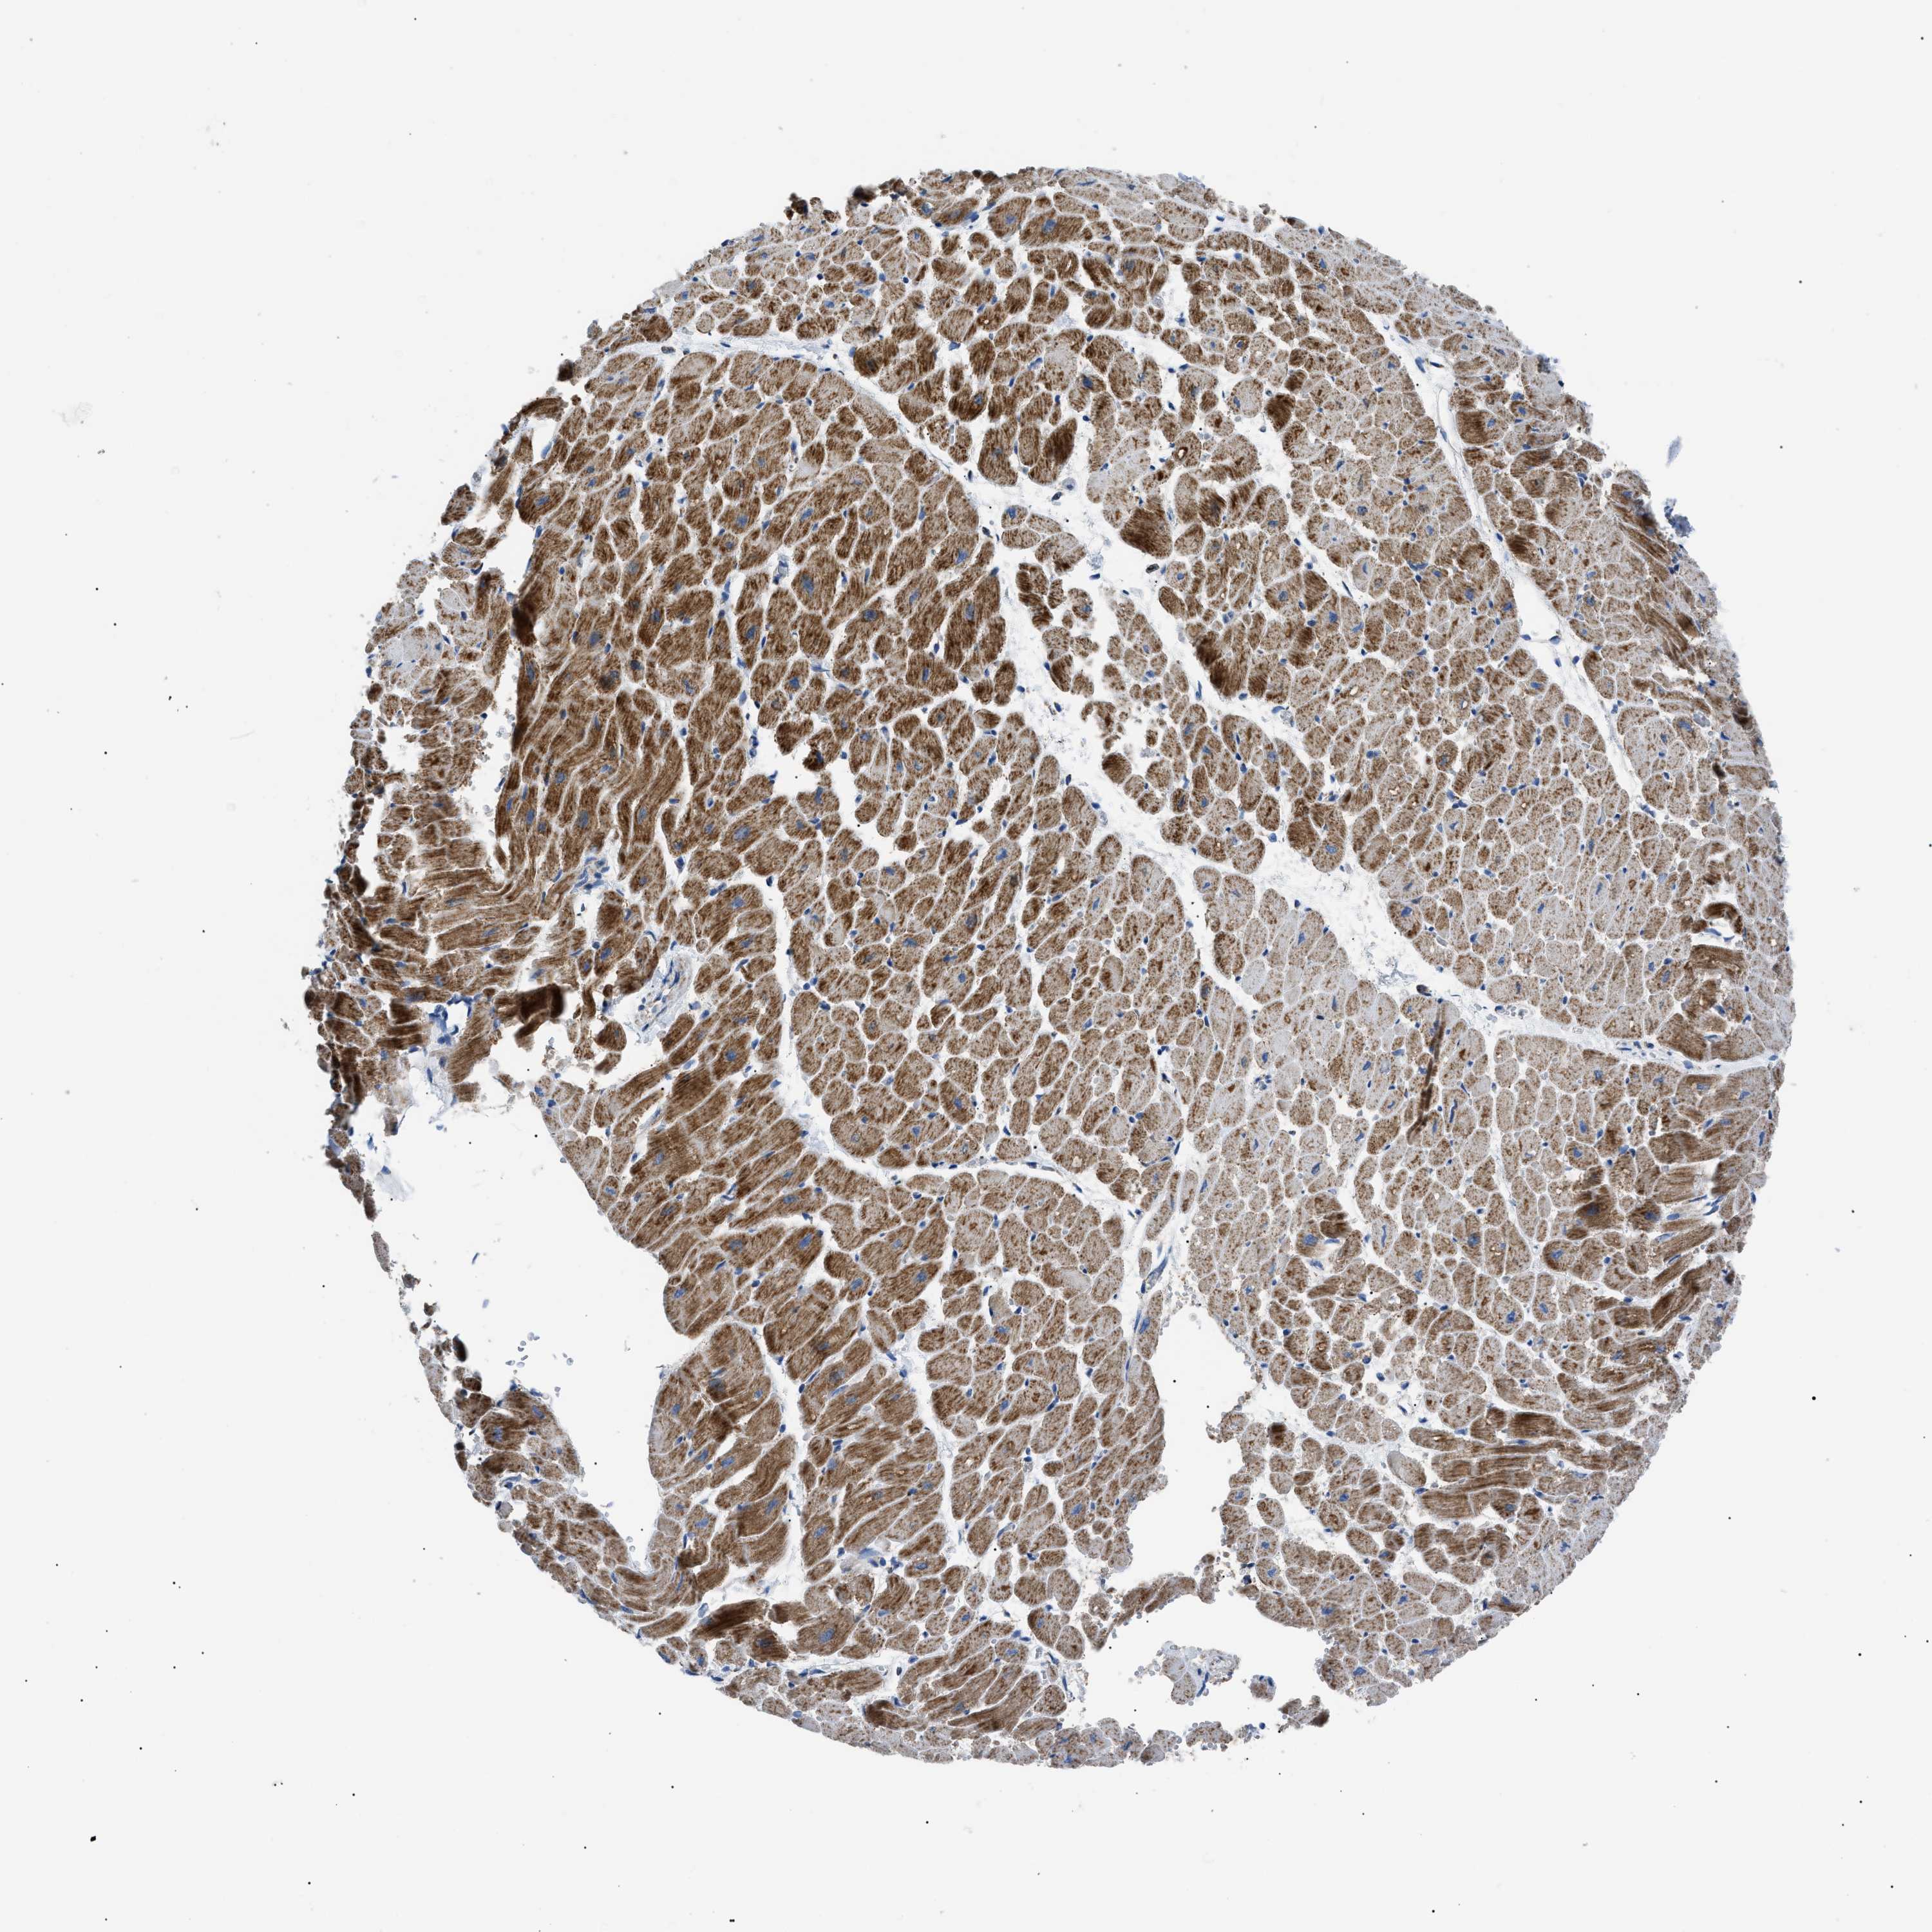

TISSUE PRIMARY DATA HEART MUSCLE Show tissue menu

HEART MUSCLE - Antibody stainingi

Antibody staining in the annotated cell types in the current human tissue is reported as not detected, low, medium, or high, based on conventional immunohistochemistry profiling in selected tissues. This score is based on the combination of the staining intensity and fraction of stained cells.

Each image is clickable and will lead to virtual microscopy that enables deeper exploration of all samples and also displays staining intensity scores, fraction scores and subcellular localization as well as patient and tissue information for each sample.

Antibody HPA039874Antibody CAB014889Antibody CAB026335

Cardiomyocytes MediumHighHigh